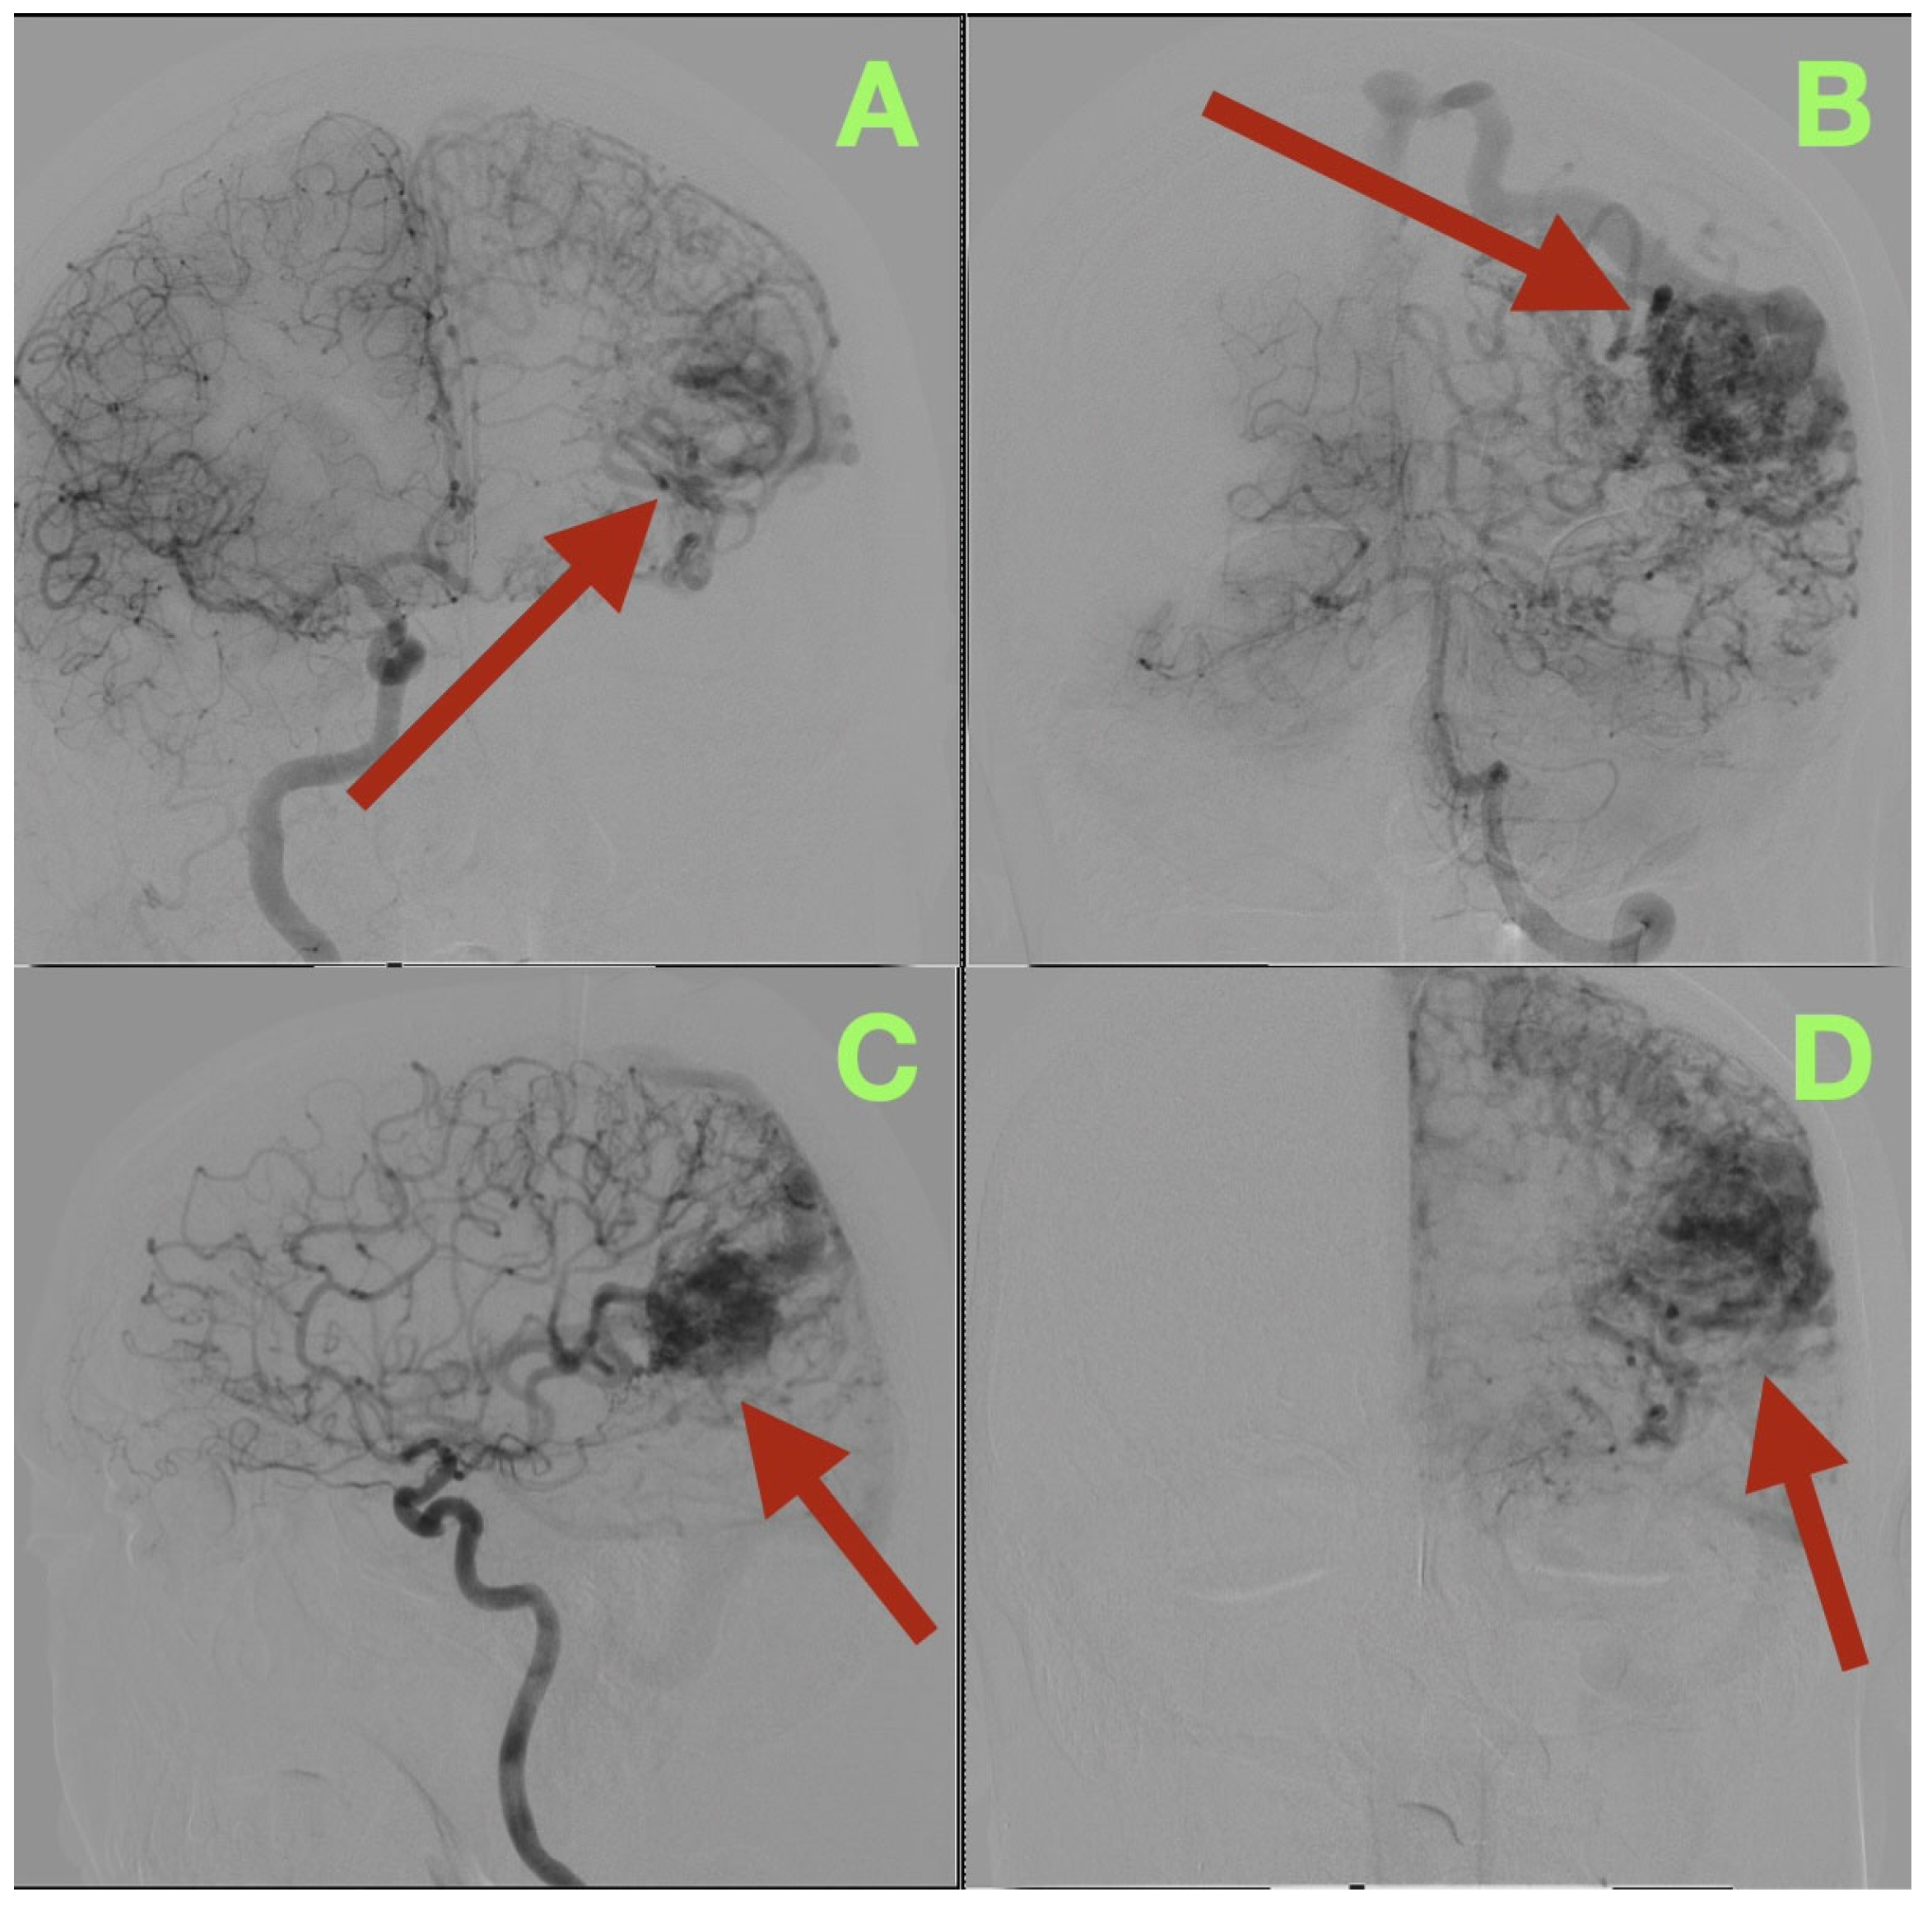

Additionally, a control CT scan was performed at the time of this visit (Figure 4). This study confirmed that the patient’s surgical site had healed well. The post operative cavity located at the left temporo-parieto-occipital junction was clean and clearly defined from the surrounding brain tissue with no evidence of residual vascular structures, hemorrhage or edema. The surrounding brain tissue was noted to be within normal attenuation values and the ventricles and midline structures were intact and unchanged. These findings were consistent with the complete removal of the malformation and restoration of normal cerebral anatomy.